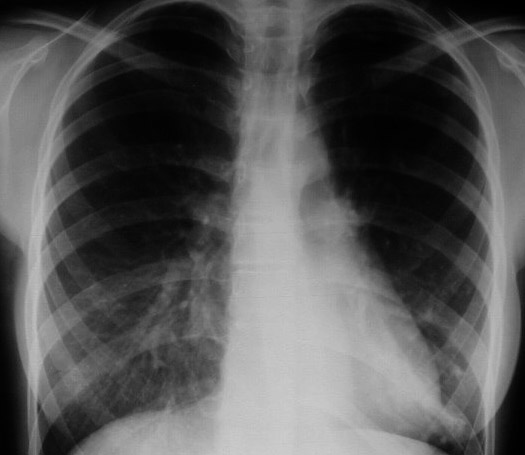

Signo de colapso del lóbulo superior izquierdo en la radiografía posteroanterior de tórax. Consiste en la hiperclaridad o lámina aérea alrededor del arco aórtico (flechas) producida por la hiperinsuflación del lóbulo inferior izquierdo, que asciende hasta el vértice pulmonar. El segmento 6 contacta con la parte posterior del botón aórtico, permitiendo que éste sea visualizado con gran nitidez.

El nombre del signo corresponde a los términos germanos luft (aire) y sichel (hoz).

La proyección lateral confirma el colapso del lóbulo superior izquierdo, manifestado por el aumento de densidad anterosuperior, el desplazamiento anterior de la cisura mayor y la hiperinsuflación del lóbulo inferior.